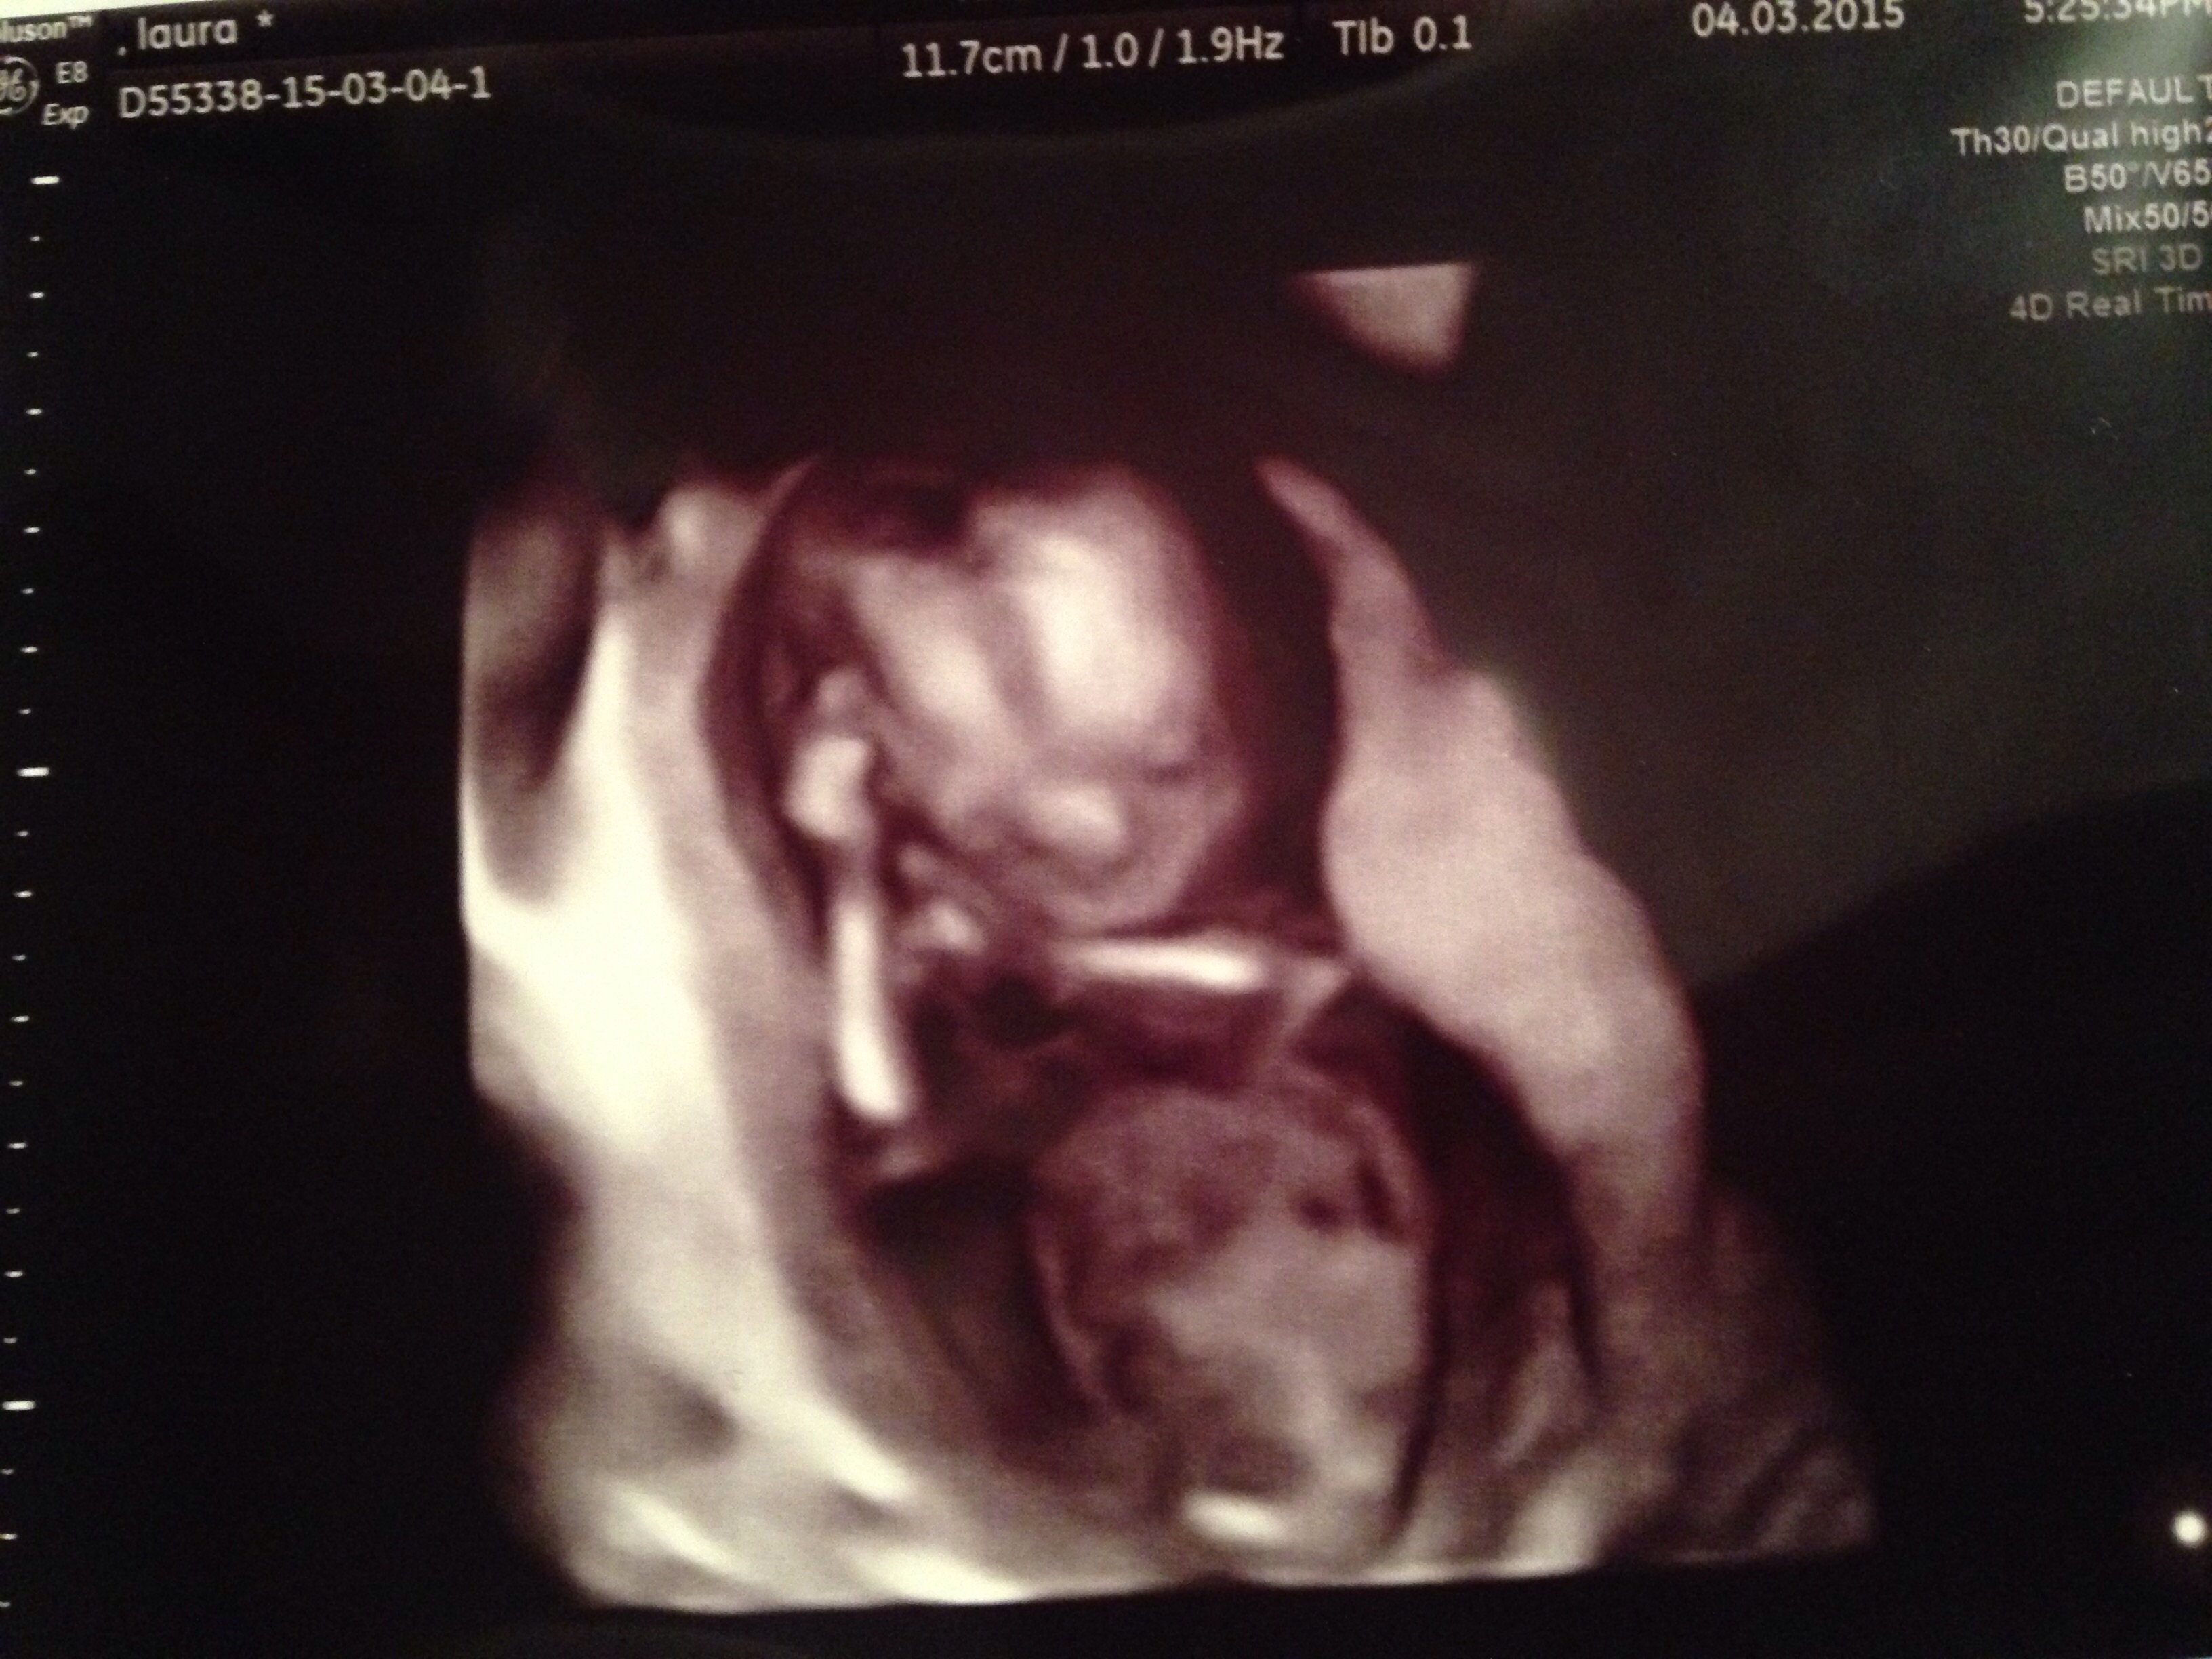

Attachment 23995Hi guys! Gender scan tomorrow at 16+6! (Anticipation took over lol!!!) this scan is 13+1.. My babies nub is very flat (girly) but has something on the end (boyish) can anyone shine light on this? I always thought the nub theory was the 'angle of the dangle?' Does my babies nub go against this? Place your guesses guys I will update you all when I find out! Thank you all xxx